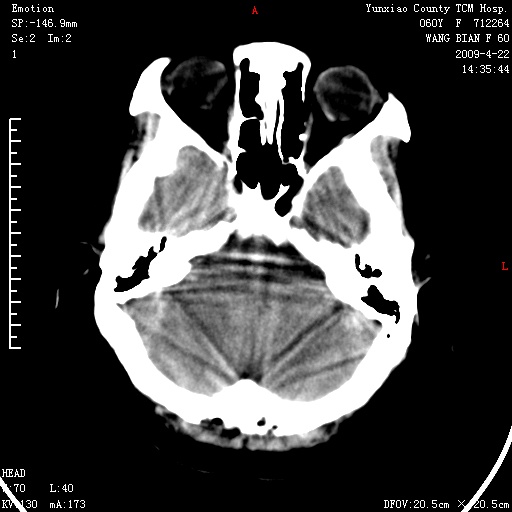

标题: CT19525:体检

蛛网膜颗粒压迹 左肾低密度影囊肿可能。

1、头颅未见明显异常。

1、头颅未见明显异常。2、左肾囊肿可能。建议增强

1、枕骨蛛网膜粒压迹。2、左肾囊肿可能。建议增强

1)枕骨蛛网膜粒压迹。2)左肾囊肿可能。